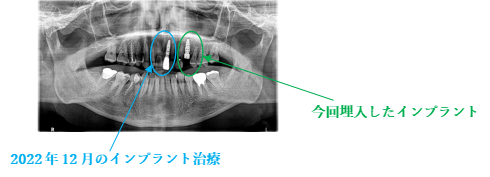

所感

2022年12月に左前歯が歯根破折を起こして抜歯しました。歯がなくなったところは、インプラント治療をして、インプラントの良さを実感しておられましたので、今回も左上の抜けたところを補う方法に、ブリッジではなくインプラントを選択されました。今回もX-Guideを使った埋入で、安心安全に行うことできました。

インプラント1本:¥363,000(税込)

2022年2月のインプラント治療